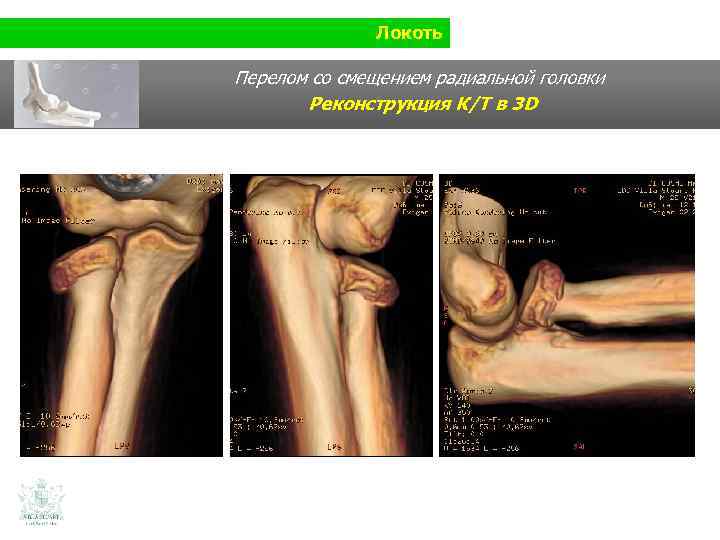

Локоть Перелом со смещением радиальной головки

Локоть Перелом со смещением радиальной головки Реконструкция К/Т в 3 D